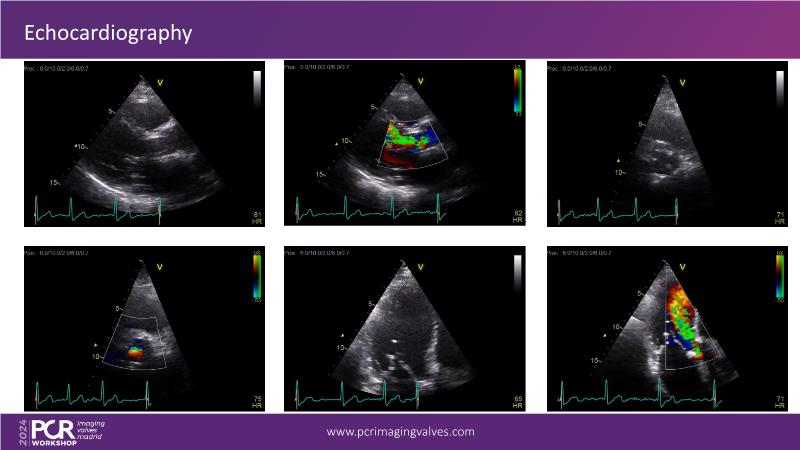

Explore cutting-edge transcatheter valve interventions for mitral and aortic valve disorders, including valve-in-valve procedures and management strategies for paravalvular leakages, and learn about diagnosing and treating mitral annular calcification and transcatheter options in infective endocarditis.

- To manage patients with mixed and multiple valvular heart disease: from risk stratification to therapeutic decision-making

- To get tips and tricks for guidance of transcatheter intervention